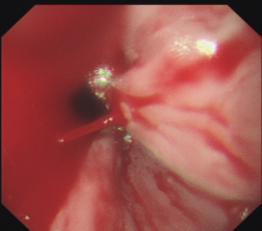

食管曲张静脉出血套扎术